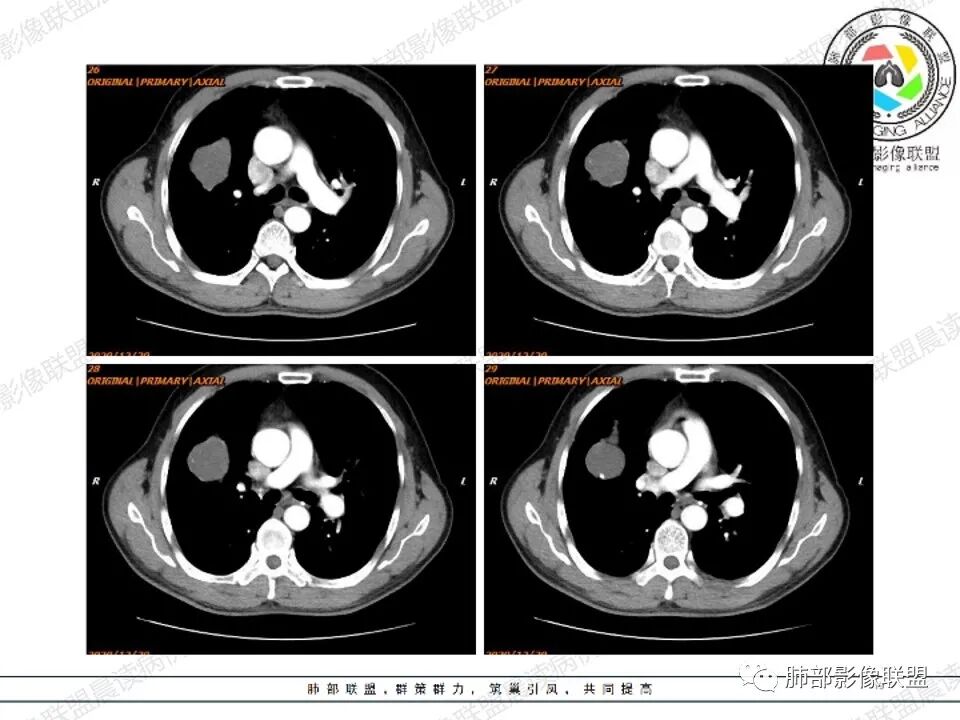

病例二

左肺下叶肿块影平行支气管生长,边缘有纤维索条影,整体边缘平直,略彭隆,边界清楚,伴行支气管堵塞,周围伴有肺气肿,增强扫描强化不明显,无明显实性病变,考虑良性,支气管闭塞?支气管囊肿?平滑肌瘤。

左肺下叶孤立性肿块,形态规则,密度均匀,边界清,周围可以气肿及条索,无强化,左肺下叶后基底段支气管未见发育?考虑发育畸形,支气管囊肿 ?闭锁?先天性囊性腺瘤样畸形?

老年女性,查体发现,左肺下叶不规则实性肿块,边缘平直收缩,无毛刺,周围有纤维牵拉及肺气肿,强化不明显。先天肺发育不良,支气管闭锁。

左肺下叶扁平形结节,边缘光滑平直,边界清晰,周围肺气肿,强化不明显,支持先天肺发育不良,支气管囊肿

左肺下叶不规则高密度早灶,边缘平直为主,界清,周围有肺气肿,无强化,考虑良性病变,支持先天肺发育异常,支气管闭锁,鉴别支气管囊肿,囊腺瘤样畸形。

左肺下叶高密度,边缘光滑,周围肺气肿,强化不明显,ccam?鉴别 隔离

左肺下叶肿块,边缘光滑,支气管动脉伴行,周围肺气肿,考虑支气管闭锁